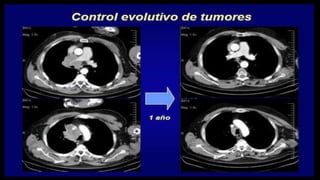

El documento define los conceptos básicos de pixeles, voxels y principios de calidad de imagen en tomografía computarizada. Explica que los pixeles son unidades de información en una imagen y los voxels son unidades de volumen que representan pixeles en secciones de corte. También describe factores como resolución espacial, de contraste y temporal que afectan la calidad de imagen, así como posibles artefactos.